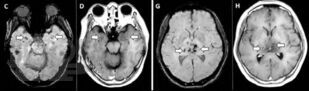

Пособие подготовлено в соответствии с требованиями ФГОС ВО по специальности 31.05.01 Лечебное дело, действующего учебного плана и рабочей программы (2020 г.) для изучения дисциплины «Неврология, нейрохирургия». В нем излагаются современные представления об этиопатогенезе новой коронавирусной инфекции COVID-19, подходы к ее диагностике и лечению, а также клинические особенности поражения нервной системы.

Отдельно рассмотрена организация медицинской помощи пациентам неврологического профиля в условиях распространения COVID-19. Уровень изложения материала соответствует современным требованиям и позволяет оптимизировать организацию и управление самостоятельной работой обучающихся. Пособие содержит тестовые задания и ситуационные задачи, которые помогут в изучении неврологической аспектов COVID-19.